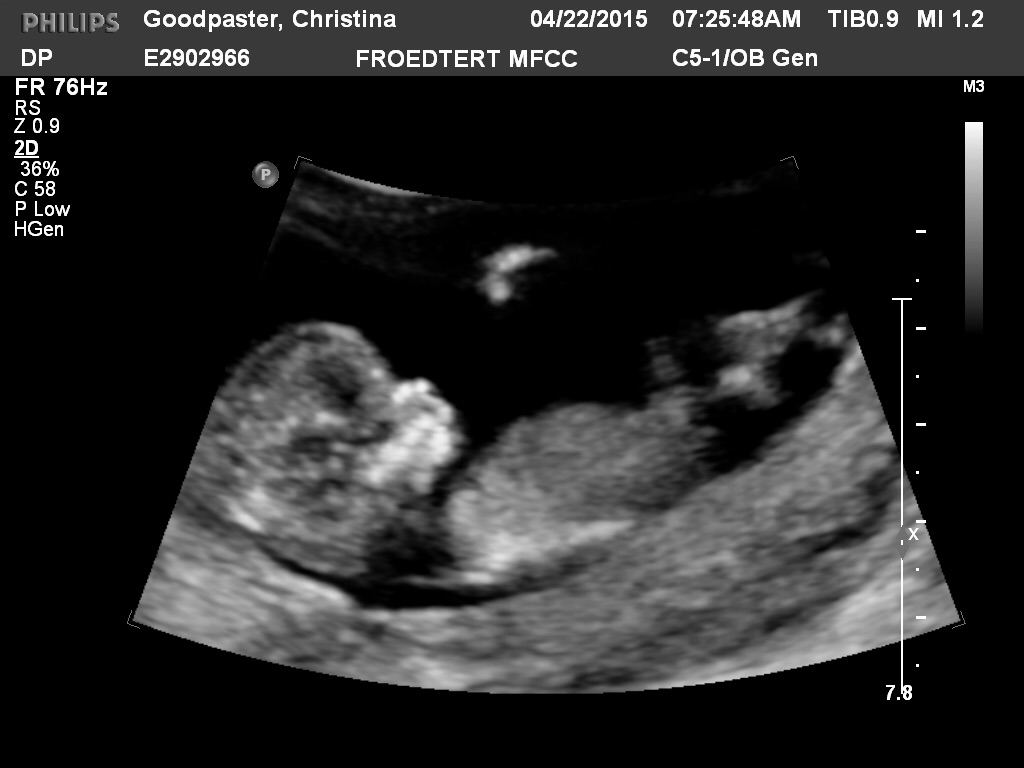

All looked good in the scan. Wiggles was moving all around and being really cute. The tech took a guess at the gender and we will get the results of all of the bloodwork next week. I'm just feeling happy. Look at those cute legs! Hope everybody gets good scans and has a great week.

I felt like I had a sore uterus the day after too. The office didn't realize that I was doing the nt scan so they didn't tell me to have a full bladder. We still saw wiggles just fine but I think she had to get in deep to do so.